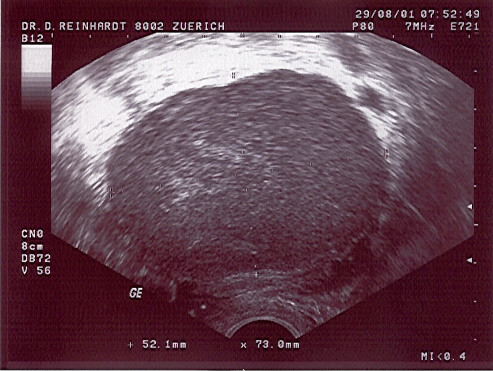

Endometriosecyste im Ultraschall und gleicher Befund intraoperativ